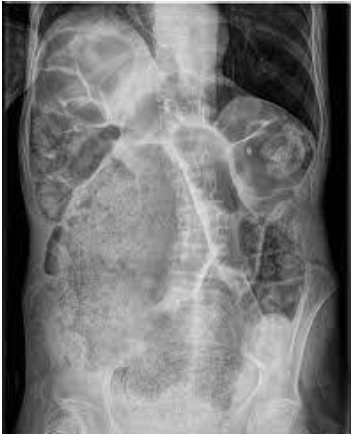

Rx simple de abdomen: se aprecia una imagen de ocupación del colon izquierdo “en miga de pan”.